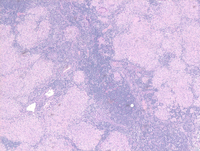

Asbestos bodies can be seen in peribronchiolar macrophages (a), intraalveolar space (b), and alveolar septum or interstitium (c and d). Langerhans giant cells are seen with lamilated basophilic calcifications known as schaumann bodies or asteroid bodies. Oval, concentrically laminated intracytoplasmic inclusions asteroid bodies: Schaumann bodies are the inclusion bodies usually seen in sarcoidosis, but can also be found in other conditions like. Schaumann (conchoidal) bodies are concentrically lamellated calcified nodules seen within the cytoplasm of multinucleated.

Lymph node biopsy with Schaumann bodies. Download Scientific Diagram Schaumann Bodies And Asteroid Bodies Seen In Schaumann (conchoidal) bodies are concentrically lamellated calcified nodules seen within the cytoplasm of multinucleated. Oval, concentrically laminated intracytoplasmic inclusions asteroid bodies: Asbestos bodies can be seen in peribronchiolar macrophages (a), intraalveolar space (b), and alveolar septum or interstitium (c and d). Langerhans giant cells are seen with lamilated basophilic calcifications known as schaumann bodies or asteroid bodies. Schaumann bodies are. Schaumann Bodies And Asteroid Bodies Seen In.